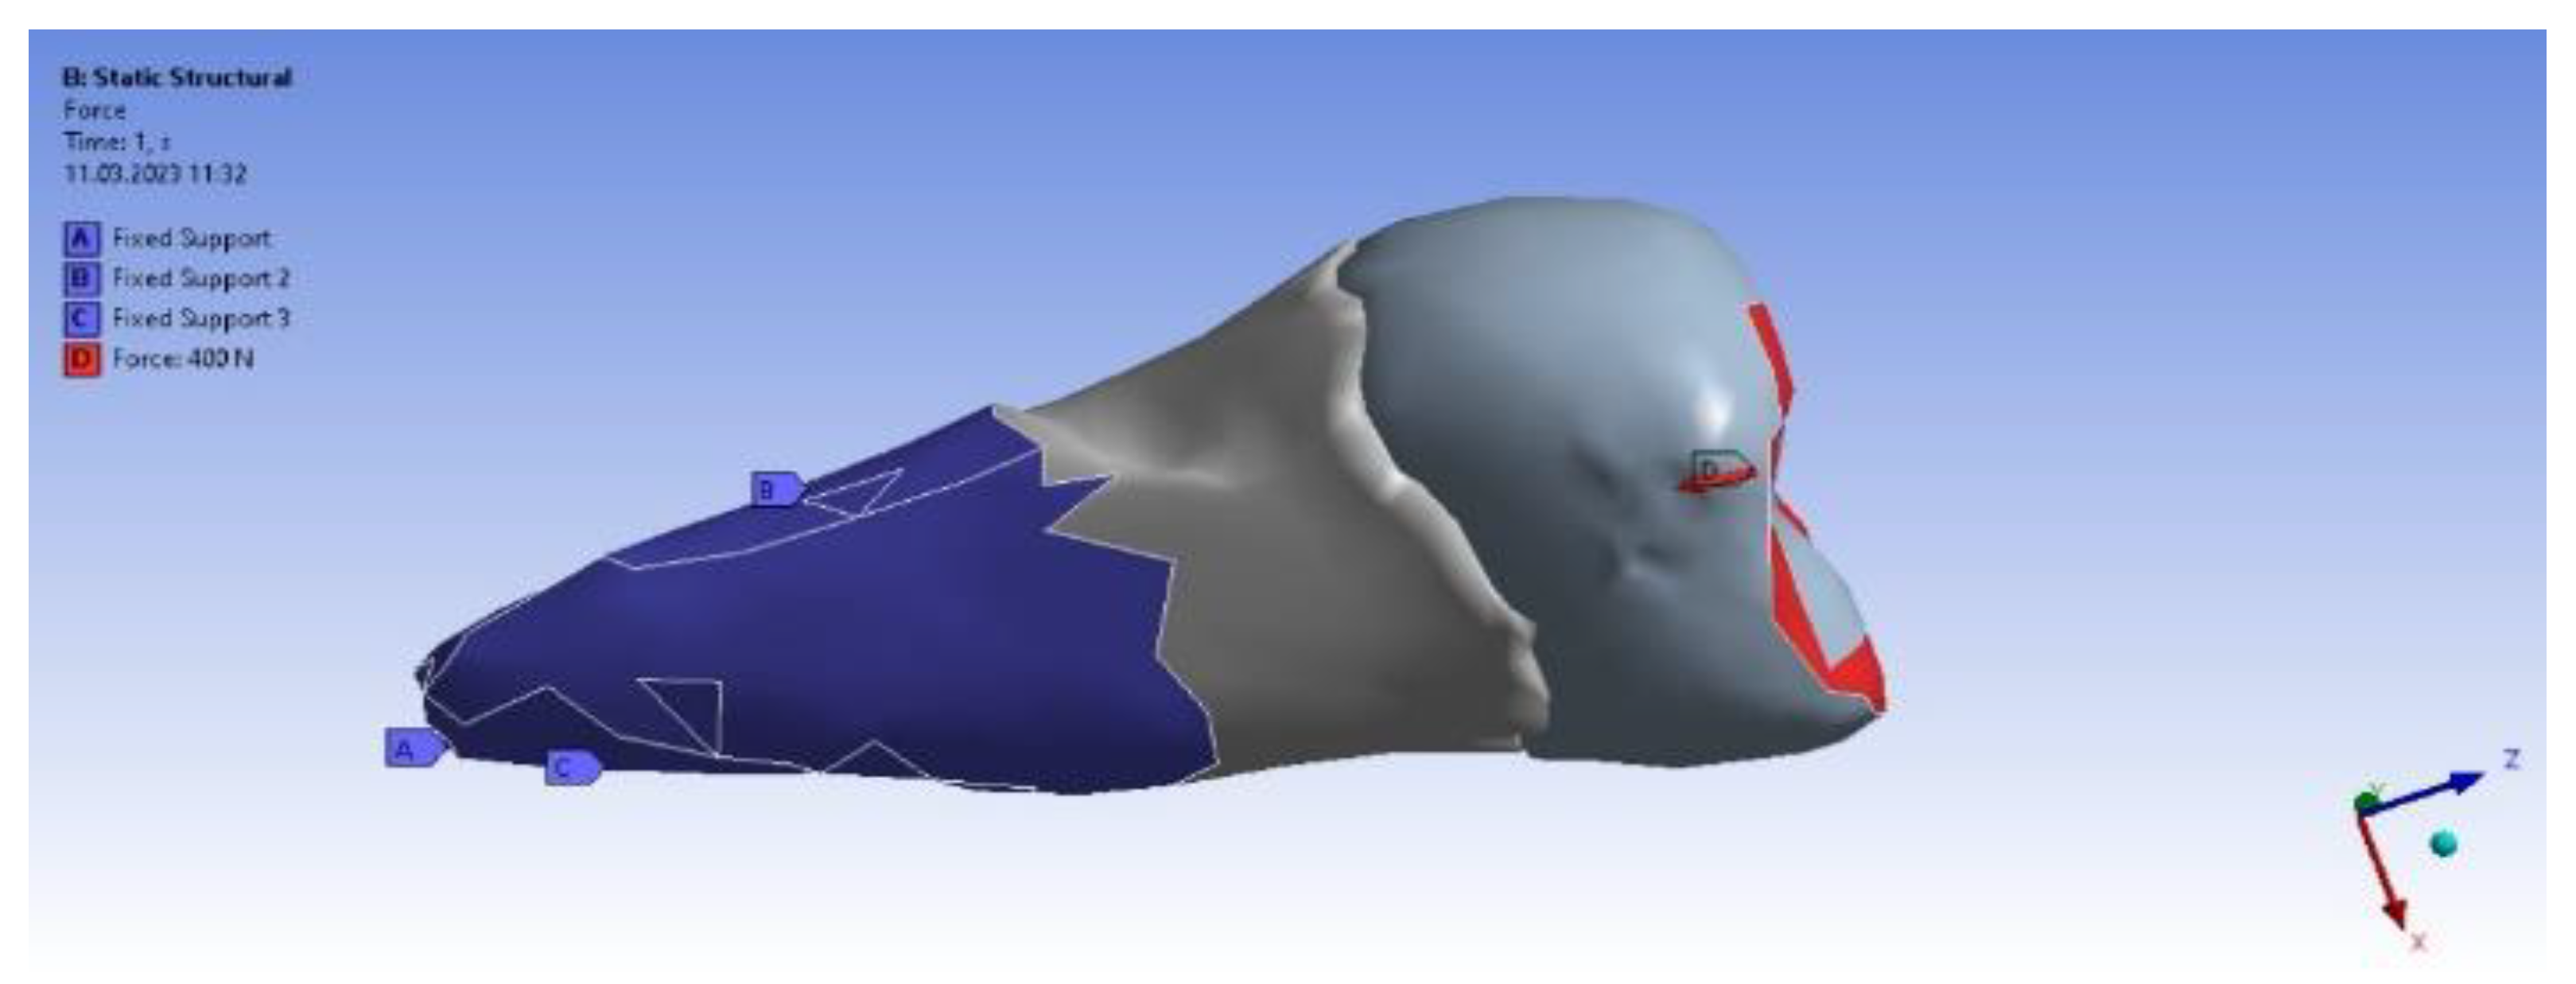

In the analyzed case, we selected the Static Structural calculation mode, within which the objects that, through their geometry, constitute the model and the properties of the materials involved in the calculations (Engineering Data) were defined. Next, the definition of the Support (support of the volumetric element) and the means of applying mechanical stress (Force) were determined. In the Solution section, the mechanical elements that required calculation by FEA were determined. The adjacent diagram shows the requirements. Then, the program started to find results in the Solution section. In the case of the second premolar, the support area A inside the alveolus (blue area) and the area B for applying the pressure force to the occlusal surface (red areas) were defined (Figure 8).

Figure 8.

Definition of support area and force application areas.

In the Engineering Data (Figure 9), the material constants characterizing the tooth required for performing the analysis with finite elements were entered. A force of 400 N at 35 °C was used in two positioning variants: perpendicular to the tooth crown and inclined at 45°, to simulate mastication (the first variant) and stress due to bruxism (the second variant).